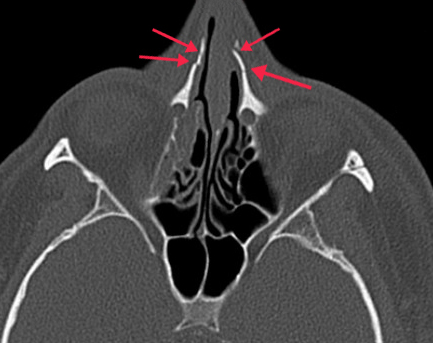

코뼈골절의 경우 신속하고 섬세한 수술이 매우 중요한데 이는 제대로 된 치료를 받지 않으면 추후 코가 휘거나 가라앉는 등 기형이 생길 수 있기 때문이다. 특히나 코뼈는 인근 얼굴뼈와 연관되어 있기 때문에 전체적인 얼굴 비율을 감안하여 수술해야 불균형을 방지할 수 있다. 따라서 수술 전 X-ray나 CT 촬영 등 세밀한 검사는 필수이며 풍부한 수술 경험이 있는 전문의와 충분한 상담이 필요하다. 수술 과정은 기계적으로 진행되는 것이 아닌 전문의가 직접 실시하기 때문에 수술 역량에 따라 결과 차이 또한 크다.

1차적인 수술이 성공적으로 끝났어도 세월의 흐름과 2차적인 외부 충격에 의해 얼굴 변형이 일어나기 쉽기 때문에 이상을 느낀다면 다시 검사를 받아보는 것이 좋다. 강남역 오페라성형외과 정경인 원장은 "요즘과 같은 겨울철에 미끄러지거나 장난을 치다가 비골골절이 발생하는 경우가 많다. 충격을 받았음에도 외관상 문제가 없다고 그냥 방치하게 되면 추후 매부리코나 휜코로 발전 할 수 있기 때문에 빠르게 내원하여 상담 및 검사를 받는 과정이 필요하다"고 전했다.